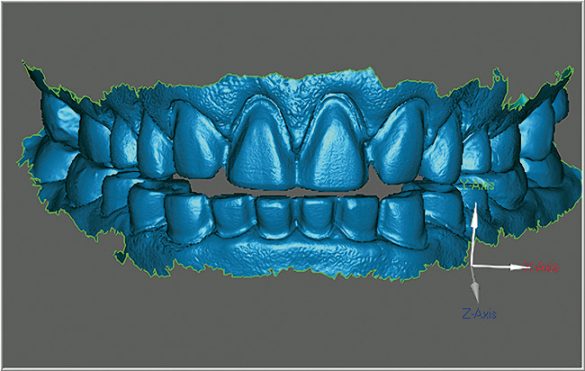

După finisarea preparaţiilor, retracţia s-a obţinut utilizând o pastă de retracţie gingivală. Materialul solid disponibil în seringă este simplu de folosit şi delicat faţă de ţesutul gingival. După aplicarea unui strat subţire de pulbere de contrast, s-a utilizat un aparat de scanare orală pentru a captura cu precizie extremă amprentele digitale ale preparaţiilor, cu o rezoluţie crescută, alături de înregistrările ocluzale.17 Acest sistem este unic datorită utilizării tehnologiei de capturare video tridimensională şi permite utilizatorului să verifice dacă toate componentele critice ale amprentei sunt obţinute prin simpla monitorizare a ecranului în cursul capturării. Se pot, de asemenea, revizui marginile individuale ale preparaţiei pentru deplinătate şi detalii (fig. 5).

Este necesară doar o retracţie minimă, deoarece toate marcajele marginale, gravajul şi secţionările se efectuează virtual. În pus, procesul de prescriere este complet automat, iar informaţiile se introduc simplu pe un monitor de tip touchscreen. Fişierul se trimite apoi prin email pentru procesarea modelului.